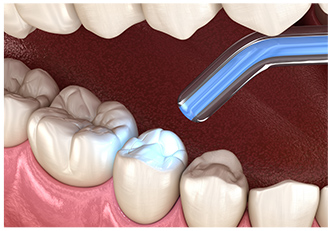

むし歯を取り除いた部分には小さな穴ができるので、細菌が入り込まないように「コンポジットレジン」といわれる歯の色に似た詰め物で塞ぎます。

むし歯になった部分を削り、そこにコンポジットレジンと呼ばれる歯科用プラスチックを充填します。

従来の詰め物の治療より歯を削る量を抑えられます。

歯を削った部分の型を取り、作製したインレーを歯科用接着剤で合着します。

インレーの種類は患者さんのご要望に合わせてご提案いたします。